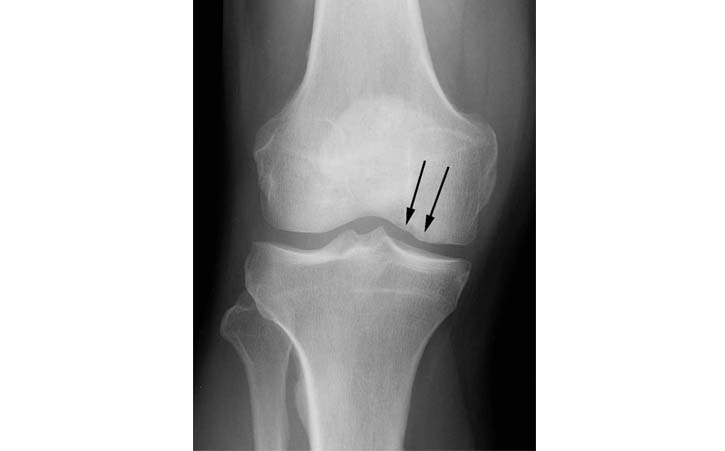

The patient is a 40 year old male with a work related injury to his knee when lifting a 90 lbs suitcase. He had complaints of pain on the inside (medial aspect) of his knee.

1.The standard radiographs of his knee shows an irregularity of the medial femoral condyle (black arrows).